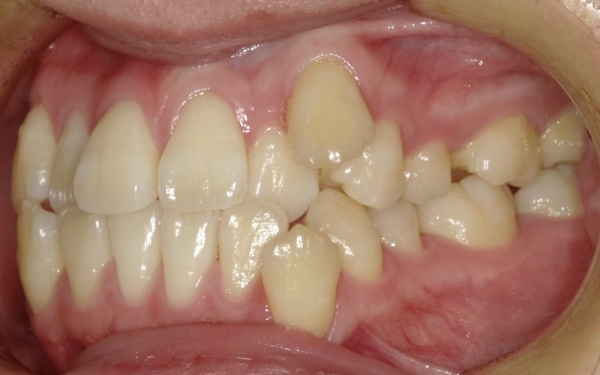

20代女性 八重歯と前歯のガタつきをマルチブラケット装置とアンカースクリューの併用で改善した症例

治療前

カウンセリング・診断結果 拝見したところ、上下左右の前歯と前から5番目までの小臼歯は、歯が生えそろうスペースが不足し、歯が正常な位置からずれたりねじれたりしてガタガタに生えている「叢生(そうせい)」の状態です。

また、上左右の側切歯は下左右の側切歯の内側に噛み込んでおり、噛み合わせが反対になる「クロスバイト」が見られます。

さらに、上下左右の犬歯は他の歯と比べて低い位置に生えて唇側へ傾いている「低位唇側傾斜」です。